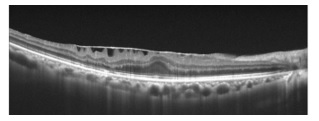

網膜静脈閉塞症

網膜静脈閉塞症は網膜の静脈が血栓などにより閉塞し、出血する疾患です。黄斑部に浮腫が生じる場合(黄斑浮腫)があり、その場合視力が低下することがあります。黄斑浮腫の治療としてステロイドや抗VEGF薬の注射などがあります。また、血流の不良の場所に網膜光凝固(レーザー治療)を行うこともあります。硝子体出血を起こした場合には硝子体手術を行うこともあります。